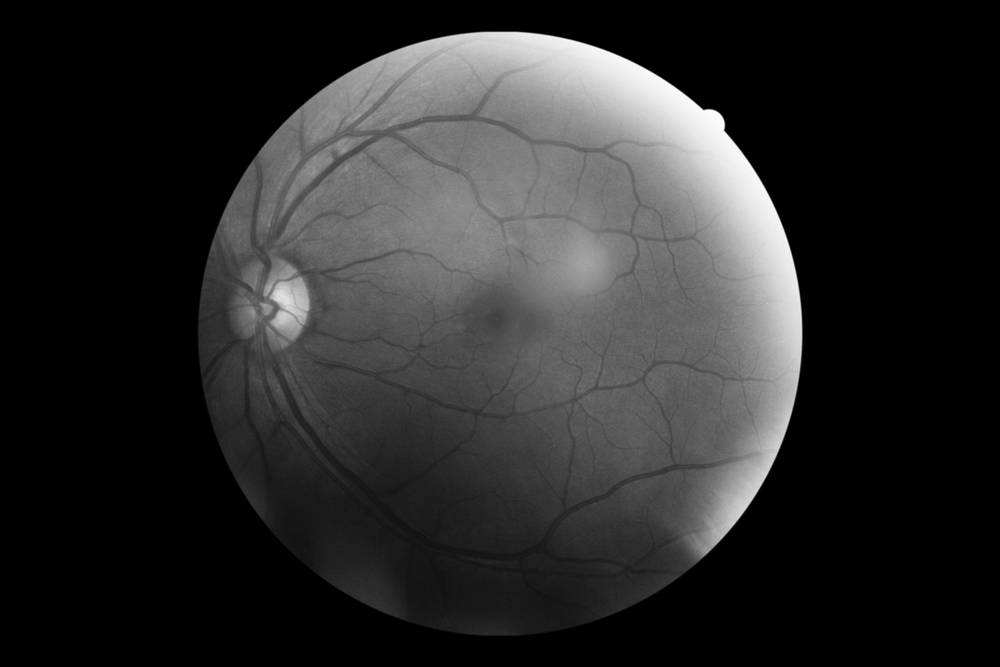

眨眼造成的“视觉空白”可能只是视觉错觉的冰山一角,事实上,即使在你的眼睛完全睁开的时候,所获得的也只是一部分视觉信息。在视网膜的中心,有一个约1毫米直径的部分,那里布满了密集的感光细胞,被称为视网膜的中央凹,

是视觉系统接受视觉信息的最佳位置,也是对视觉信息细节和色彩感知力最强的地方。雷恩辛克指出:“在视网膜的除中央凹之外的其他地方,视觉灵敏度大为下降,而色觉则完全消失。而在偏离中央凹的边侧处,视觉灵敏度只有最强视觉的20%。”

这也就意味着,在某个任意时刻,你的眼睛只能捕获到视野中全部色彩和细节的一小部分。伸直你的手臂,然后看你的拇指盖,这就是视网膜中央凹覆盖的大致范围,而视网膜其余部分捕获的视觉信息只是一片模糊的黑白图像。